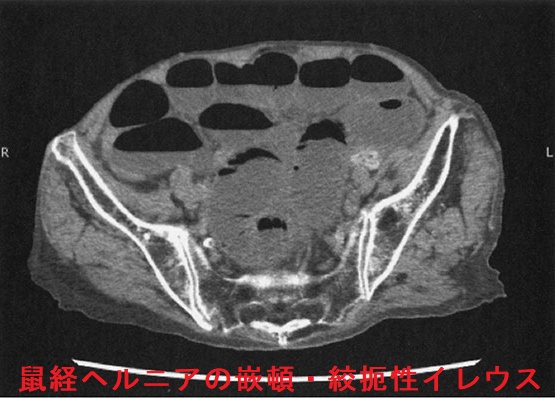

外鼠径ヘルニア(間接鼠径ヘルニア)では、腸管が内鼠径輪→鼠径管を経て外鼠径輪に脱出。陰嚢腫大は外鼠径ヘルニア特有の症状です。内鼠径ヘルニアに比べてヘルニア門が狭く嵌頓(かんとん)しやすい。

CT画像でヘルニア門が下腹壁動脈の外側なら外鼠径ヘルニア、内側なら内鼠径ヘルニアです。

CT検査は臥位でおこなうため、腹圧が下がりヘルニアが改善するので病変を見逃す可能性があります。例え、仰臥位のCT撮影でヘルニアを明瞭に描出できなくても、腹臥位なら診断できる場合があります。